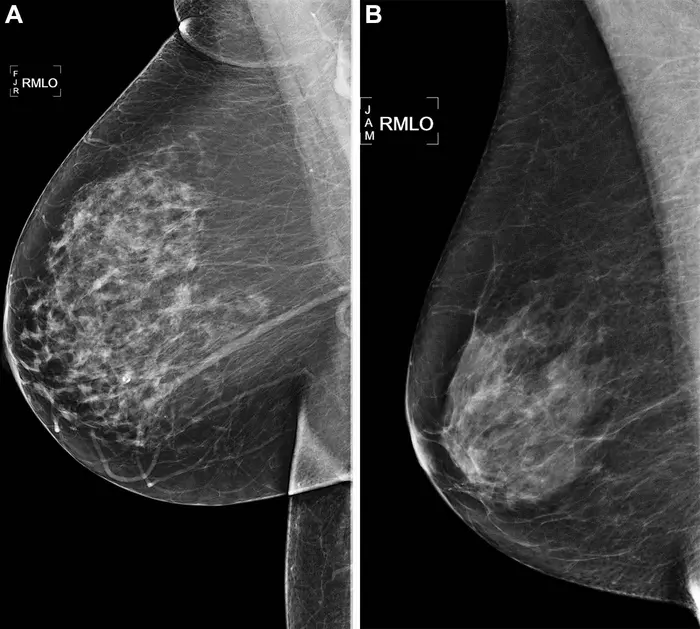

Vrouwen bij wie borstkanker in de familie voorkomt of die andere redenen hebben om aan te nemen dat ze een verhoogde kans lopen op de ziekte, kunnen een medisch onderzoek laten uitvoeren om hun individuele risico uit te laten rekenen. Er wordt dan een scan van hun borsten gemaakt – een mammogram – en de artsen nemen andere relevante informatie, zoals hun leeftijd, erfelijke belasting, de dichtheid van de borsten en of de vrouw kinderen heeft gekregen, mee in hun berekening. Een veelgebruikt klinisch risicomodel dat deze data samenvoegt, is het Breast Cancer Surveillance Consortium (BCSC)-model.

De onderzoekers deelden de vijfjarige studieperiode op in drie delen: het directe kankerrisico, waarbij binnen een jaar borstkanker werd geconstateerd; het toekomstige kankerrisico, waarbij de diagnose tussen een jaar en vijf jaar na de mammografie plaatsvond en het totale kankerrisico, waarbij alle diagnoses meetellen. De AI-algoritmes kregen alleen de mammografie-foto uit 2016 om mee te werken, terwijl bij de handmatige BCSC-methode veel meer informatie werd meegewogen. Toch wisten de AI-modellen op mysterieuze wijze bovenaan te eindigen in het onderzoek. “Alle vijf AI-algoritmes presteerden beter dan het BCSC-risicomodel bij het inschatten van het risico op borstkanker binnen vijf jaar”, legt Arasu uit. “Deze geweldige prestaties laten zien dat AI in staat is om het vroegste beginstadium van kanker op te merken, maar ook bepaalde aanwijzingen in het borstweefsel, die de kans op borstkanker verder in de toekomst verhogen. Er zitten blijkbaar data in de mammogrammen verscholen die het risico op borstkanker blootleggen, maar waar het AI-model precies op aanslaat, blijft onduidelijk. Dat is onderdeel van de ‘black box’ die zo kenmerkend is voor AI-toepassingen.”

Er zijn wat verschillen tussen de vijf AI-modellen. Sommigen waren beter in het voorspellen van kanker binnen een jaar, die vaak agressiever van aard is. Een tweede mammografie is dan vaak nodig. Als we bijvoorbeeld kijken naar de vrouwen die in de 10 procent hoogste risicogroep vallen, dan voorspelt AI 28 procent van de kankers juist, terwijl BCSC maar in 21 procent van de gevallen de ziekte van tevoren kan aanwijzen. Zelfs AI-algoritmes die alleen getraind waren op kortetermijnrisico’s – maximaal drie maanden – waren in staat om vijf jaar in de toekomst te kijken en borstkanker te voorspellen die niet op de originele scan te zien was door medisch personeel. Wanneer AI en BCSC worden gecombineerd, is een nog betere kankervoorspelling mogelijk.